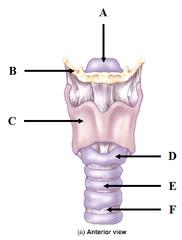

Larynx

Vocal folds (=vocal cords)

Epiglottis

C-Rings (=tracheal cartilage)